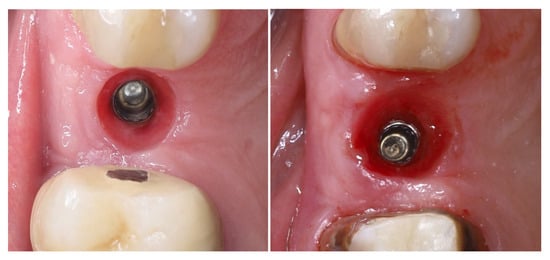

Clinical views of the implant site prior to final prosthetic restoration show a well-formed peri-implant mucosal collar with healthy soft tissue contours. The buccal mucosa demonstrates adequate thickness, consistent with the roll flap augmentation performed at the time of implant placement. The soft tissue margin appears stable without signs of inflammation, ensuring favourable conditions for the subsequent impression and definitive crown placement (left). The comparison with the situation before placement of the provisional crown (right) shows the increase in the soft tissue volume induced by the emergence profile of the crown (Figure 16).

Figure 16.

Peri-implant mucosal contours prior to definitive restoration (8 months post-op).

Figure 20 shows the dynamic of soft tissue maturation and development. The combination from soft tissue augmentation procedure with the modified roll flap and soft tissue conditioning with the temporary crown led to complete resolution of the horizontal defect of the alveolar crest and provided adequate soft tissue thickness for long-term stability of the implant-supported restoration.

Figure 20.

Dynamic of soft tissue maturation and development.